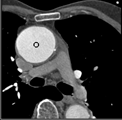

Samples for ascending aorta detection (black circle):

Cluster of candidate points in the ascending aorta.